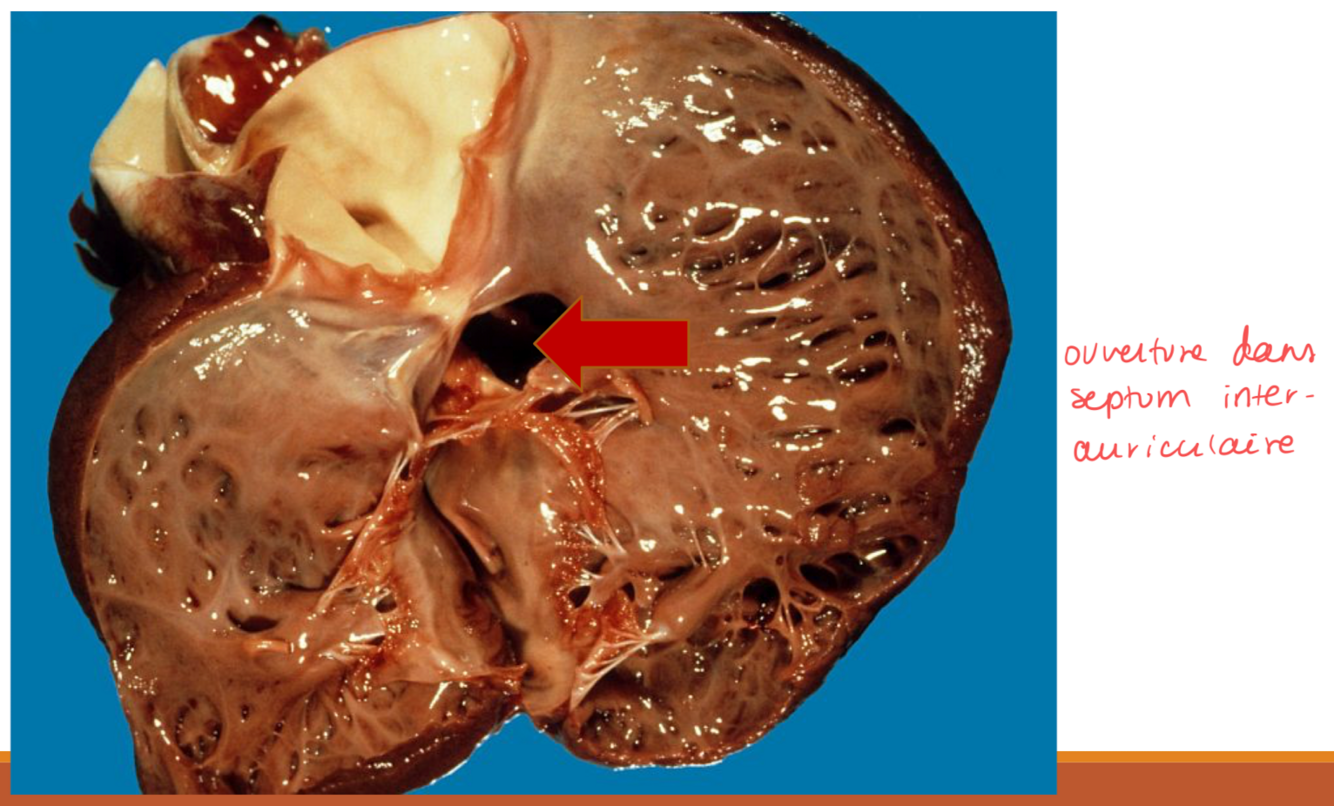

22

Q

Quelle anomalie cardiaque congénitale est présente spécifiquement chez le Samoyède ?

A

Communication interauriculaire

23

Lors de communication interauriculaire, le sang passe de où à où ?

Le sang passe de l’oreillette gauche à l’oreillette droite (shunt de gauche à droite) - car la pression est plus forte à gauche !

24

Le passage de sang de l’OG à l’OD lors de communication interauriculaire provoque quoi ?

Il y a augmentation de la pré-charge qui provoque une hypertrophie excentrique du ventricule droit.

L’augmentation de la pré-charge va aussi causer une dilatation des 2 oreillettes.